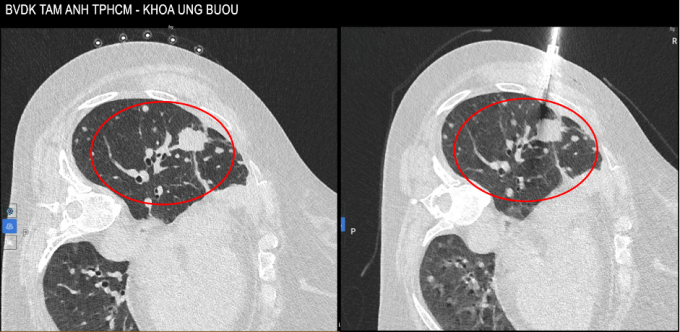

Hình ảnh CT vào tháng 10/2025 thấy u tăng kích thước lên 4 cm và các tổn thương rải rác xung quanh. Ảnh: Bệnh viện Đa khoa Tâm Anh

Bà bị đau ngực nhiều hơn, tháng 10 năm nay chụp CT phát hiện tổn thương tăng kích thước lên 4 cm. Bác sĩ chỉ định sinh thiết u phổi để tìm đột biến gene kháng thuốc. Kết quả giải phẫu bệnh và nhuộm hóa mô miễn dịch sau hai lần sinh thiết cho thấy có đột biến T790M trên gene EGFR và một số đột biến khác trên gene mTOR, TP53, làm tăng độ phức tạp của tình trạng bệnh.